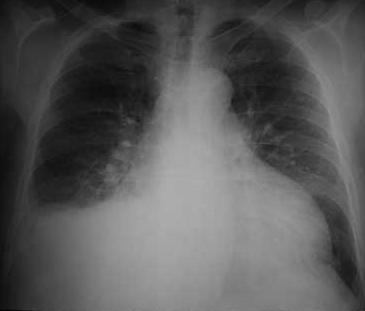

La toracocentesis es un método utilizado para el abordaje de la cavidad pleural con fines diagnósticos y/o terapéuticos. Es una maniobra dolorosa que requiere sedo-analgesia. Debe realizarse con monitorización no invasiva y clínica. Debe evitarse el uso de fármacos que produzcan depresión respiratoria. A continuación de explicará cuales son las complicaciones de la toracocentesis.

Se puede producir neumotórax por punción.

Edema pulmonar después de drenaje de grandes cantidades de líquido pleural (1000 ml).

No es necesario realizar radiografía de control luego de la toracocentesis si se va a colocar tubo de drenaje pleural y el paciente no ha sufrido agravación.